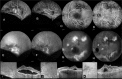

Figure 1

Figure 1. Fundus photography and ultrasonography (USG) images from the patient’s right and left eyes. A) Bullous retinal detachment extending to the superotemporal vascular arcade in the right eye; B) Serous retinal detachment in the inferior periphery and subretinal fibrin visible at the inferior and superior temporal arcades and in the nasal quadrant in the left eye; C) Retinal detachment in the inferior and superior quadrants on the USG in the right eye; D) Retinal detachment in the inferior quadrant on USG in the left eye